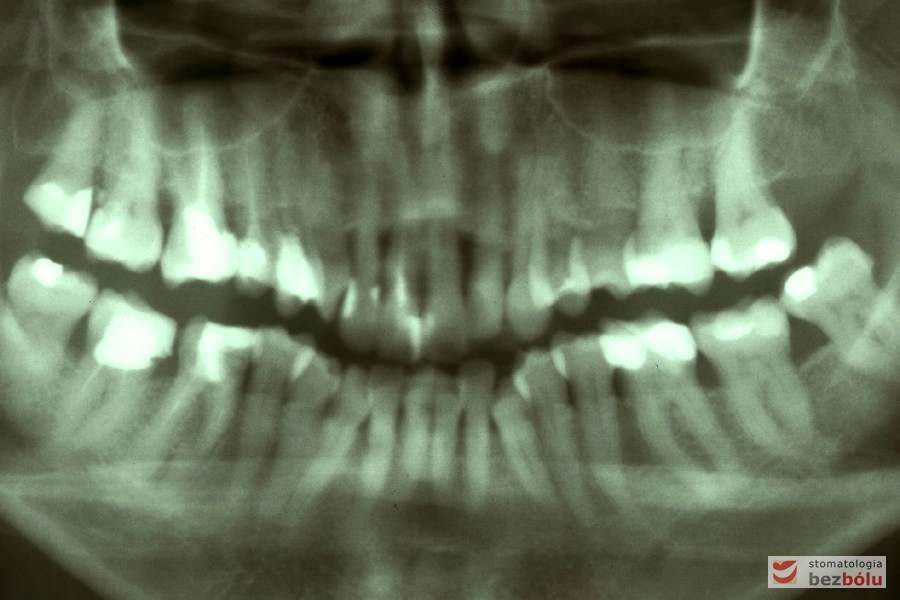

Kontrola radiologiczna - liczne zęby z niekompletną endodoncją, ubytek kości w szczęce

Kontrola radiologiczna – liczne zęby z niekompletną endodoncją, ubytek kości w szczęce